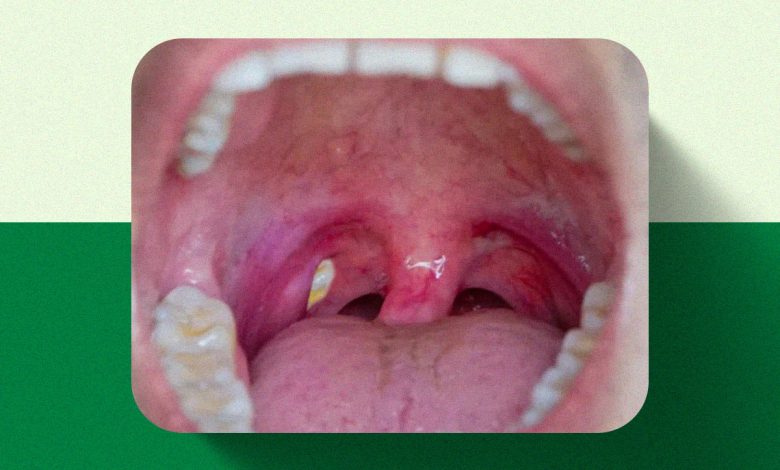

As chamadas bolinhas brancas na garganta surgem, na maioria dos casos, nas amígdalas e são formadas por restos de alimentos, células mortas e bactérias. Esse material se acumula em pequenas cavidades naturais da região e recebe o nome de caseum, também conhecido como tonsilólito.

O caseum geralmente não causa febre nem dor intensa. Já quando as bolinhas brancas aparecem acompanhadas de dor forte, febre, dificuldade para engolir e mal-estar geral, o quadro pode indicar amigdalite, que pode ter origem viral ou bacteriana e exige avaliação médica.